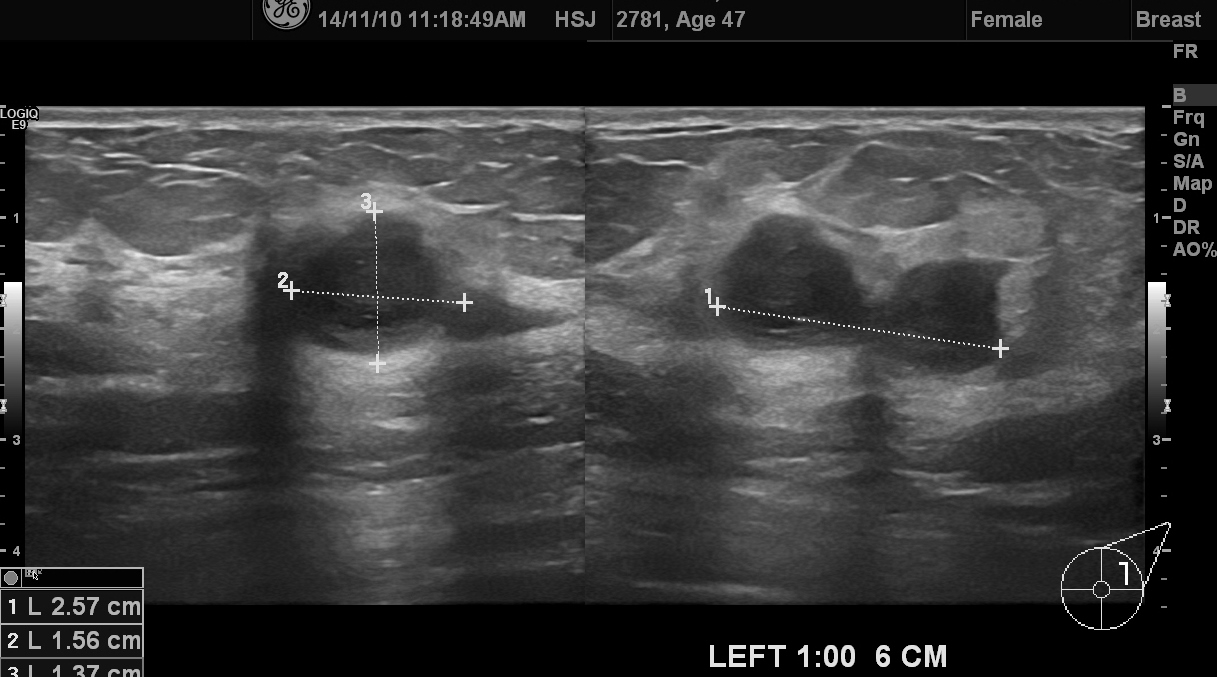

좌측 유방에 만져지는 멍우리가 있어 내원한 47세 여성입니다.

동그란 두개의 혹이 연결된 초음파 영상을 가졌고 조직검사로 침윤성 유방암이 각각 진단되셨습니다.

좌측 겨드랑이 림프절에는 암전이가 없다고 세침검사에 나와 다행입니다.